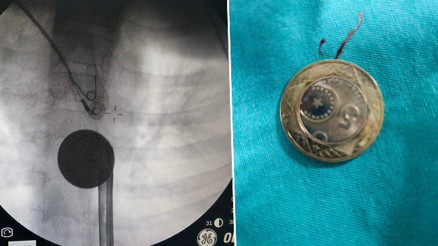

#HatayBitlis’in Tatvan ilçesinde 3 yaşındaki kızın kulağından 23 adet canlı kurtçuk çıkartıldı. Kulak Burun Boğaz Hastalıkları Uzmanı Doktor Gamze Öztürk Yılmaz, yaptığı açıklamada; bu durumun genellikle kırsal kesimlerde yaşayanlarda ve hayvancılıkla uğraşanlarda görüldüğünü söyledi. Yılmaz, "Hastamız biraz geç getirilmişti. Hastamızın şuan sağlık durumu iyi ve 2 günde bir yakın takibini sağlıyoruz." ifadelerini kullandı.

#BitlisBitlis’in Tatvan ilçesinde 3 yaşındaki kız çocuğunun kulağından 23 adet canlı kurtçuk çıkartıldı. Kulak Burun Boğaz Hastalıkları Uzmanı Doktor Gamze Öztürk Yılmaz, yaptığı açıklamada; bu durumun genellikle kırsal kesimlerde yaşayanlarda ve hayvancılıkla uğraşanlarda görüldüğünü söyledi. Yılmaz, "Hastamız biraz geç getirilmişti. Şu an sağlık durumu iyi ve 2 günde bir yakın takibini sağlıyoruz." dedi.